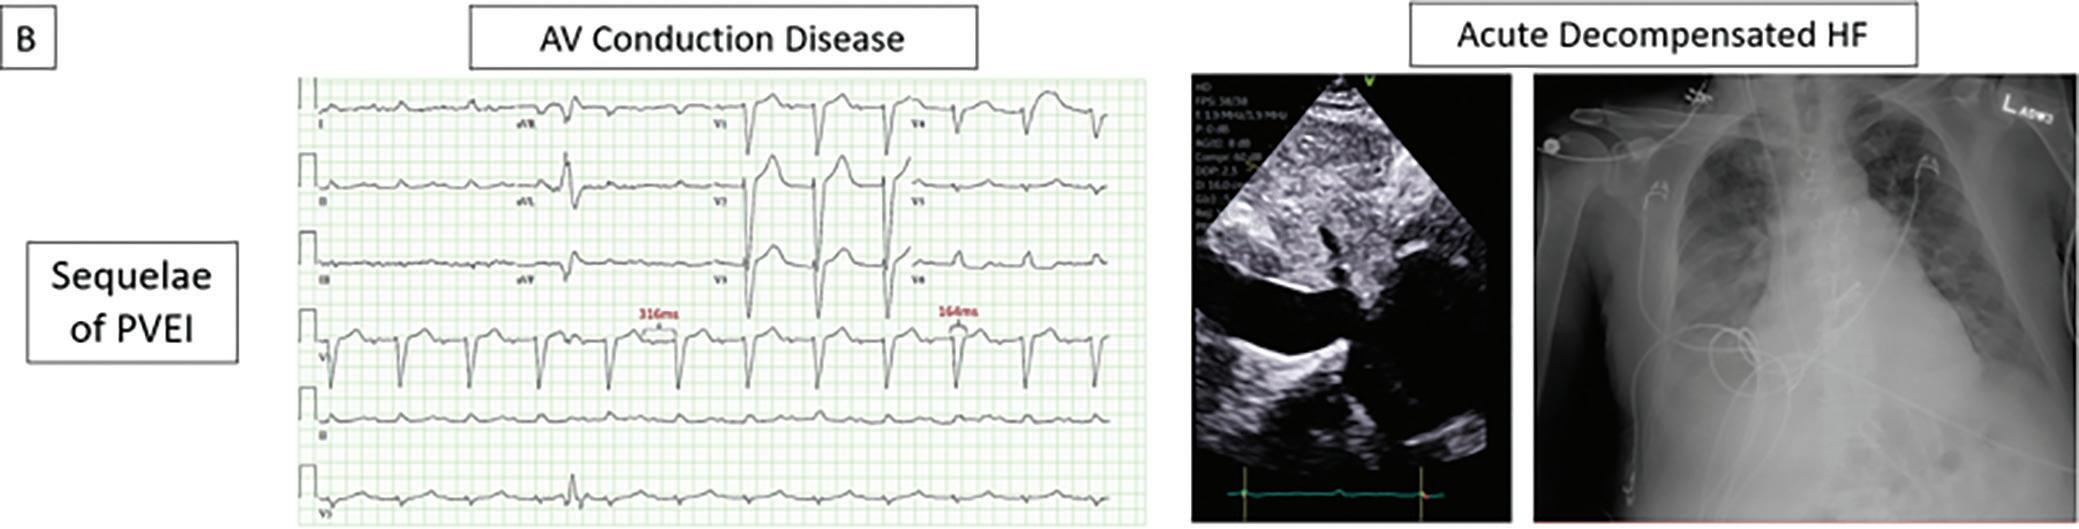

Case: A 77-year-old woman with hypertension, type 2 diabetes, and myasthenia gravis (on prednisone) presented to the hospital with complaints of worsening fatigue and shortness of breath over 1 week. The patient lost her service dog 2 weeks prior and was feeling very stressed.

She was admitted to the intensive care unit with MC and intubated for impending hypercapnic respiratory failure. The patient was started on

pyridostigmine, steroids, and plasma exchange (PLEX) treatments. During her hospital course, the patient was found to be hypotensive and developed new EKG changes (diffuse T wave inversions in anterolateral leads; Figure 1). High-sensitive troponins were in the range of 1,300–1,400 ng/dl. Transthoracic echocardiogram images without contrast (apical fourchamber view) in Figure 2A (diastole), Figure 2B (systole) revealed apical ballooning; Figure 2C (diastole) and Figure 2D (systole) with contrast confirmed the apical ballooning. Video 1 without contrast and Video 2 with contrast show the apical hypokinesia, apical ballooning, and basal hyperkinesis. Coronary angiography performed 2 years prior showed no significant coronary artery disease.

Decision-making: The patient was diagnosed with takotsubo cardiomyopathy (TTC), also called stress-induced cardiomyopathy. Stress due to the recent loss of her dog with worsening myasthenia gravis led to MC complicated with TTC. Unfortunately, in this patient, this combination was fatal.

Figure 2: Transthoracic Echocardiogram

A: diastole, and B: systole, without contrast revealing apical ballooning; C: diastole, and D: systole, with contrast confirmed the apical ballooning.